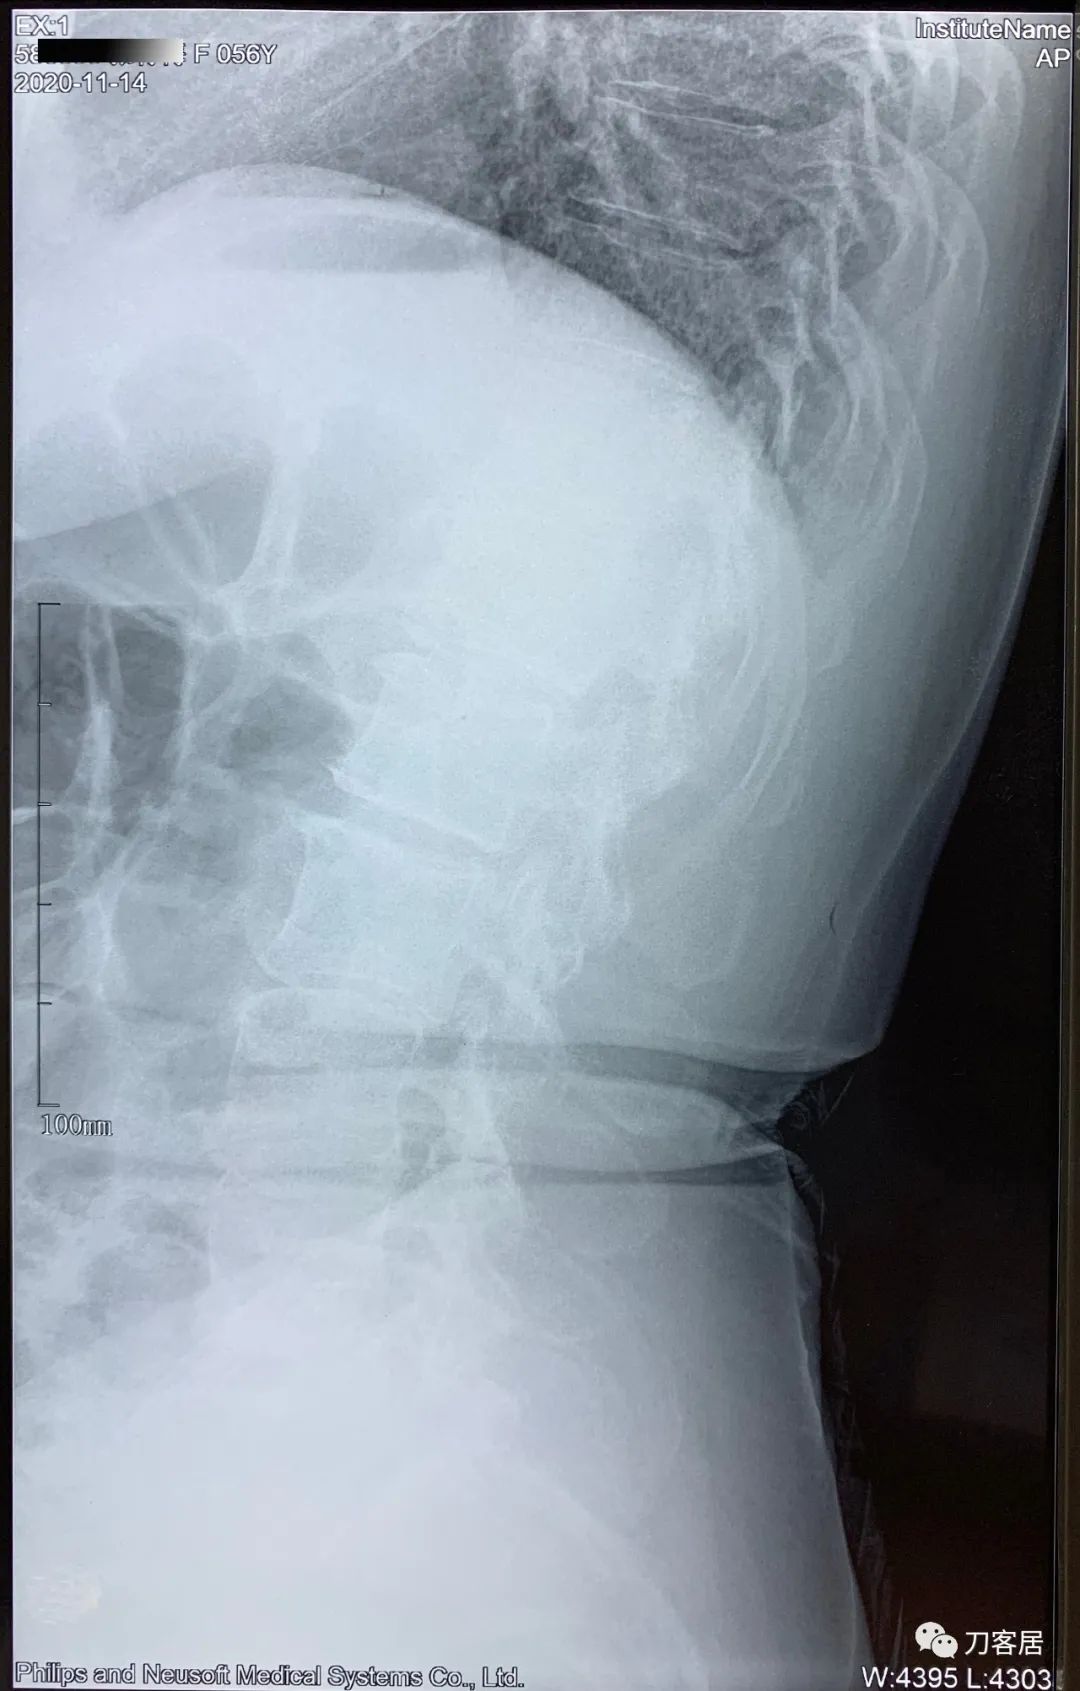

患者自2020年8月4日始头晕,2020年8月25日双手麻,双胳膊麻,于兰大二院定西分院检查颈椎MRI及腰椎X线片, 提示1. 颈椎生理曲度变直,2. 颈椎骨质增生,3. 颈椎间盘变性,颈4-7椎间盘轻度膨隆,4. 腰椎侧弯畸形。

建议其查双光子骨密度,骨盆正位片以及腰椎间盘平扫。腰椎正侧位X线片以及动力位片,站立位脊柱全长正侧位X线片,以了解其是否有骨质疏松,并了解脊柱侧弯情况,腰椎局部X线表现情况和腰椎间盘突出和椎管狭窄情况。

从这个患者的影像资料分析,颈椎间盘突出问题不大,没有明确的上位神经元损伤表现,所以,不考虑颈椎和胸椎问题。腰椎侧弯畸形,但不严重。因为存在腰椎侧弯,使得腰椎MRI在扫描切面的时候,显示的椎间盘突出或椎管狭窄会有一定的误差,所以,又加做了经椎间盘的CT平扫,影像表现并不严重,综上,腰椎间盘突出,腰椎管狭窄,腰椎侧弯,不考虑手术治疗。同时,患者的主要痛苦是心理疾病,而不是器质性疾病,所以,以心身疾病治疗为主。虽然患者骨密度检查结果提示正常,但X线片显示骨质疏松,且其症状也与骨质疏松的症状有符合之处,比如静息痛,不能入睡,动作及姿势变换时痛加重等,所以,给予实验性抗骨质疏松治疗,以观疗效。